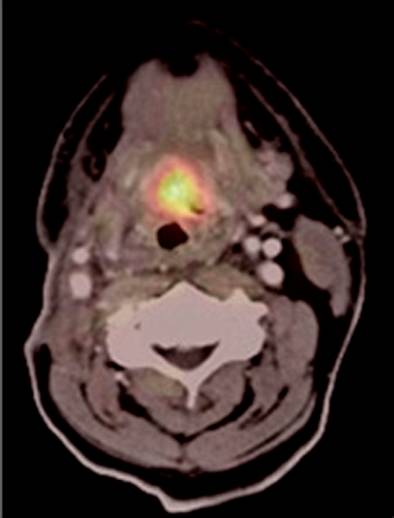

在PET/CT原型机获得的头颈部癌症患者的截面图像(1999年) (图片来自网络)

1999年6月,汤森在美国第46届核医学年会上正式发布了PET/CT原型机获得成功的消息。PET图像与CT图像的融合大大提升了图像的可读性,核医学界为此大为振奋。

有300余例肿瘤病人在这台原型机上做了检查,获得了很好的效果。医生依据检测结果可更直观、更全面、更准确地对病变作出判断,对肿瘤的早期诊断、特性鉴别、精准分期、疗效评价,对心脏及脑部疾病的诊治具有更为突出的优势。2000年10月,美国食品和药品管理局批准推出商业化PET/CT。